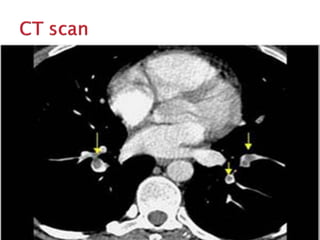

Pulmonary CT angiography is the gold

standard for diagnosis